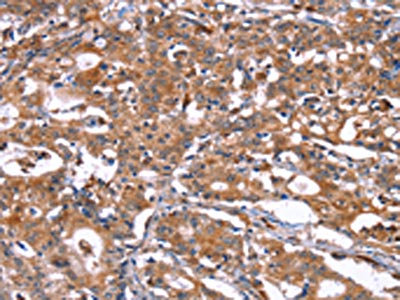

The image on the left is immunohistochemistry of paraffin-embedded Human brain tissue using CSB-PA044365(HSD17B1 Antibody) at dilution 1/40, on the right is treated with synthetic peptide. (Original magnification: ×200)

The image on the left is immunohistochemistry of paraffin-embedded Human gastric cancer tissue using CSB-PA044365(HSD17B1 Antibody) at dilution 1/40, on the right is treated with synthetic peptide. (Original magnification: ×200)